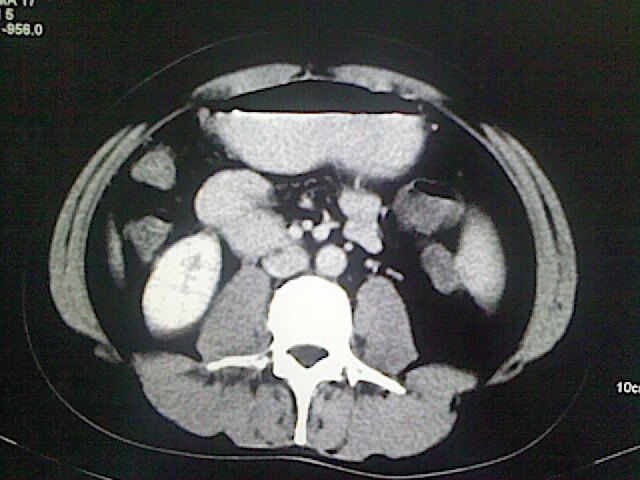

以下是引用卜一在2009-3-14 9:49:00的发言:[br]胆囊萎缩,胆囊壁不规则增厚,内部结构模糊,增强明显强化。另:肝左叶外侧段肝囊肿。支持:慢性胆囊炎!高度可疑:胆囊癌!

以下是引用余辉在2009-3-14 8:48:00的发言:[br]1)慢性胆囊炎。2)肝左叶外侧段肝囊肿。3)脂肪肝。[br]支持,胆囊萎缩,密度增高,不知b超具体有何提示,钙胆汁?结石?

以下是引用jiangjing在2009-3-14 10:18:00的发言:[br]1)慢性胆囊炎。2)肝左叶外侧段肝囊肿。3)脂肪肝。4.】建议行肝功能检查